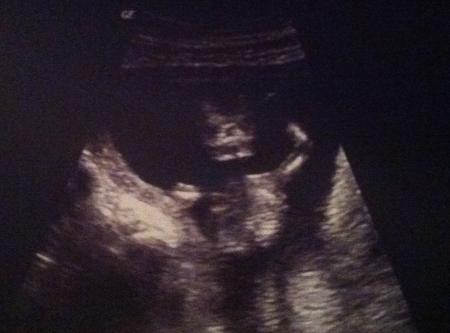

Endlich, endlich hatte ich heute auch meinen Termin zum Erstsemester-Screening. Blut abnehmen hab ich tapfer überstanden (ich kann keine Nadeln sehen...) und dann gings ab zum Ultraschall. Das Baby war richtig aktiv, hat gewunken, gestrampelt und sich fleißig gedreht. Der Arzt war ganz zufrieden und meinte, es sieht alles gut aus, inklusive Nacken. Haben auch die kleinen Füßchen gesehen, die Wirbelsäule und erste Rippchen. Eigentlich bin ich heute bei 12+5, aber wie beim letzten Mal ist das Kleine schon fast eine Woche weiter. Der Arzt hat's auf 13+3 vordatiert und meinte, dass wir evt. auch den voraussichtlichen Entbindungstermin nach vorne verschieben. Weil das Baby so lustig gewunken hat (und mein Arzt ganz viele Bildchen gemacht hat ), haben wir noch ein bisschen weitergeguckt und dann wurde er ernster und meinte "Hm!" Er hat sich dann die Nackenfalte nochmal genauer von der anderen Seite angesehen, als der Wurm anders lag und hat erst 2,6 mm gemessen und dann nochmal 2,9. Normal wäre bis 3 - also schon ziemlich oberer Grenzwert. Allerdings hat er das auch relativiert und meinte, dafür dass ich schon so weit bin und das Baby und somit ja auch die Nackenfalte wächst, sei das kein Grund zur Beunruhigung. Normalerweise macht man die NFM ja zwischer der 10 und 13.Woche - und da bin ich dann ja auch schon oberes Ende. Trotzdem hat uns das erstmal beunruhigt! Naja, ich denke jetzt positiv und warte auf die Blutergebnisse nächste Woche. Anbei ein Foto von unserem kleinen Rennfahrer Outingtechnisch hat sich das Kleine noch bedeckt gehalten...

Bild zu Nackenfalten-Messung - Forum für April - Mamis